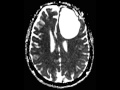

Neuroepithelial Ependymal Cyst

This is a case of a neuroepithelial ependymal cyst. There is a well circumscribed cystic lesion with a thin, nearly imperceptible wall. The cystic contents demonstrate mild FLAIR-hyperintense signal, no diffusion restriction, and no increased blood volume on the contrast enhanced perfusion map. There is no postcontrast enhancement. The lesion demonstrates moderate localized mass effect resulting in effacement of the surrounding cerebral cortical sulci and associated effacement and deformity of the frontal horn and body of the left lateral ventricle. Neuroepithelial ependymal cysts are benign neuroepithelial cysts with an ependymal lining. The majority of lesions are asymptomatic, due to their small size. Larger lesions are associated with symptoms due to the associated mass effect and midline shift. Most cases present in young adults with a slight male predominance. The differential diagnosis includes perivascular cysts, neurocystercercosis, and porencephalic cysts.